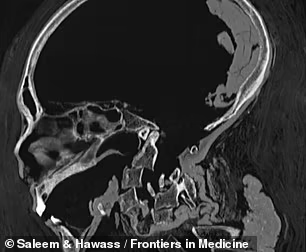

据外媒报道,近日,开罗大学医学院的研究人员通过CT三维重建,恢复了距今有大约有3500年历史的古埃及法老,阿蒙霍特普一世的生前面目。

为此,研究人员决定对阿蒙霍特普一世进行CT三维重建,这将有助于了解他最初怎么被制作成木乃伊的,以及死后被盗墓贼破坏后,后人又是如何修复他的。

结果发现,阿蒙霍特普一世的身高大约为168厘米,牙齿很好,他还接受过割礼。其相貌与他的父亲十分相似,下巴和鼻子都很窄小,头发卷曲,上牙略微突出。此外,研究人员还发现了30个护身符和一条十分独特的金腰带。

研究人员表示,CT图像同时揭示了阿蒙霍特普一世木乃伊的损伤程度,其颈部有骨折并被斩首,前腹壁缺失了一大块,并且四肢也与身体脱离。

遭到了严重破坏后,其后人将他脱离的肢体放回原位,并用树脂将这些肢体与身体固定在一起,并用新绷带重新对其进行了包扎。